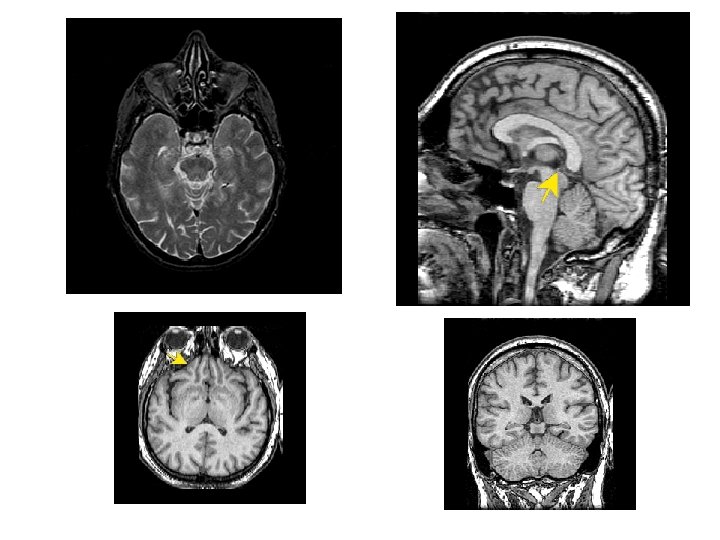

MRI • NOT IONIZING RADIATION • USES MAGENTIC RESONANCE • (RADIO WAVES) • Jane Schultz, R. T. (MR) 51

53

RADIOGRAPHY VS MRI BONE vs. Soft Tissue 55